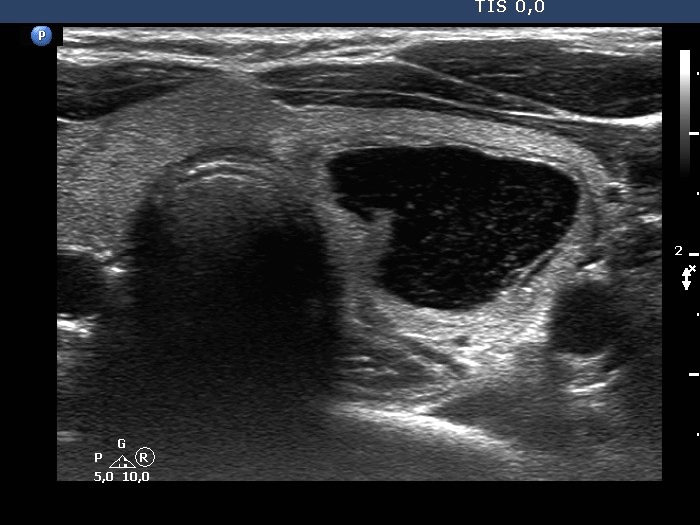

First examination (first row of images):

Clinical presentation: A 36-year-old woman noticed enlargement of the left thyroid after an upper airway infection.

Palpation. The left lobe had an elastic nodule.

Result of blood test: TSH 1.69 mIU/L.

Ultrasonography. The thyroid was echonormal. There was a central-type cystic lesion in the left lobe. The cystic part presented numerous echogenic granules without a tail.We aspirated 5 mL bloody fluid. Aspiration cytology resulted in non-diagnostic cystic lesion.